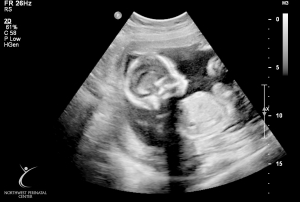

Last Ultrasound